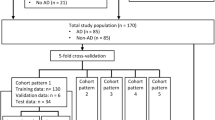

Between 2015 and 2019, 130 arterial phase series (57 type A, 43 type B, and 30 negative cases) in aortic CTA were collected for the training and validation. A 2-step hierarchical model was built including the first step detecting AD and the second step predicting the probability (0–1) of Stanford types. The model’s performance was evaluated with an off-line prospective test in 2020. The sensitivity and specificity for Stanford type A, type B, and no AD (Sens A, B, N and Spec A, B, N, respectively) and Cohen’s kappa were reported.